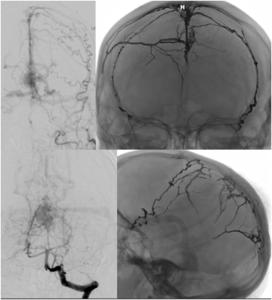

Brain Arteriovenous Malformation (AVM) Embolization

An Arteriovenous malformation or AVM is an abnormal connection between arteries and veins, bypassing the capillary system. This vascular anomaly is widely known because of its occurrence in the central nervous system, but can appear in any location. Although many AVMs are asymptomatic, AVMs in the brain can cause intense headache, intracranial bleeding, and/or lead to other serious medical problems, such as seizures. Vascular malformations can be treated endovascularly with embolization using liquid embolics, such as Onyx and n-BCA, by open surgery, or by gamma knife radiosurgery. Sometimes these lesions are treated by a combination of the above mentioned therapies.

Dural Arteriovenous Fistula (AVF) Embolization

A duralarteriovenous fistula (DAVF) is an abnormal direct connection (fistula) between a meningealartery and a meningeal vein or dural venous sinus. Like other vascular malformations, a dural AVF can be treated endovascularlywith embolization using liquid embolics, such as Onyx and n-BCA, by open surgery, or by gamma knife radiosurgery. Sometimes these lesions are treated by a combination of the above mentioned therapies.

Spinal AVF Embolization

Most spinal fistulas are created when a radiculomeningeal artery feeds directly into a radicular vein near the spinal nerve root. Spinal dural AVFs are most commonly found in the thoracolumbar region. Patients become symptomatic because the AVF creates spinal cord venous congestion and hypertension, resulting in hypoperfusion, hypoxia, and edema of the spinal cord. Due to the slow-flow nature of most spinal dural AVFs, hemorrhage rarely occurs. Most dural AVFs are believed to occur spontaneously, but the exact etiology is still unknown. Again, these types of vascular lesions can be treated endovascularly with embolization using liquid embolics, such as Onyx and n-BCA, and with open surgery.